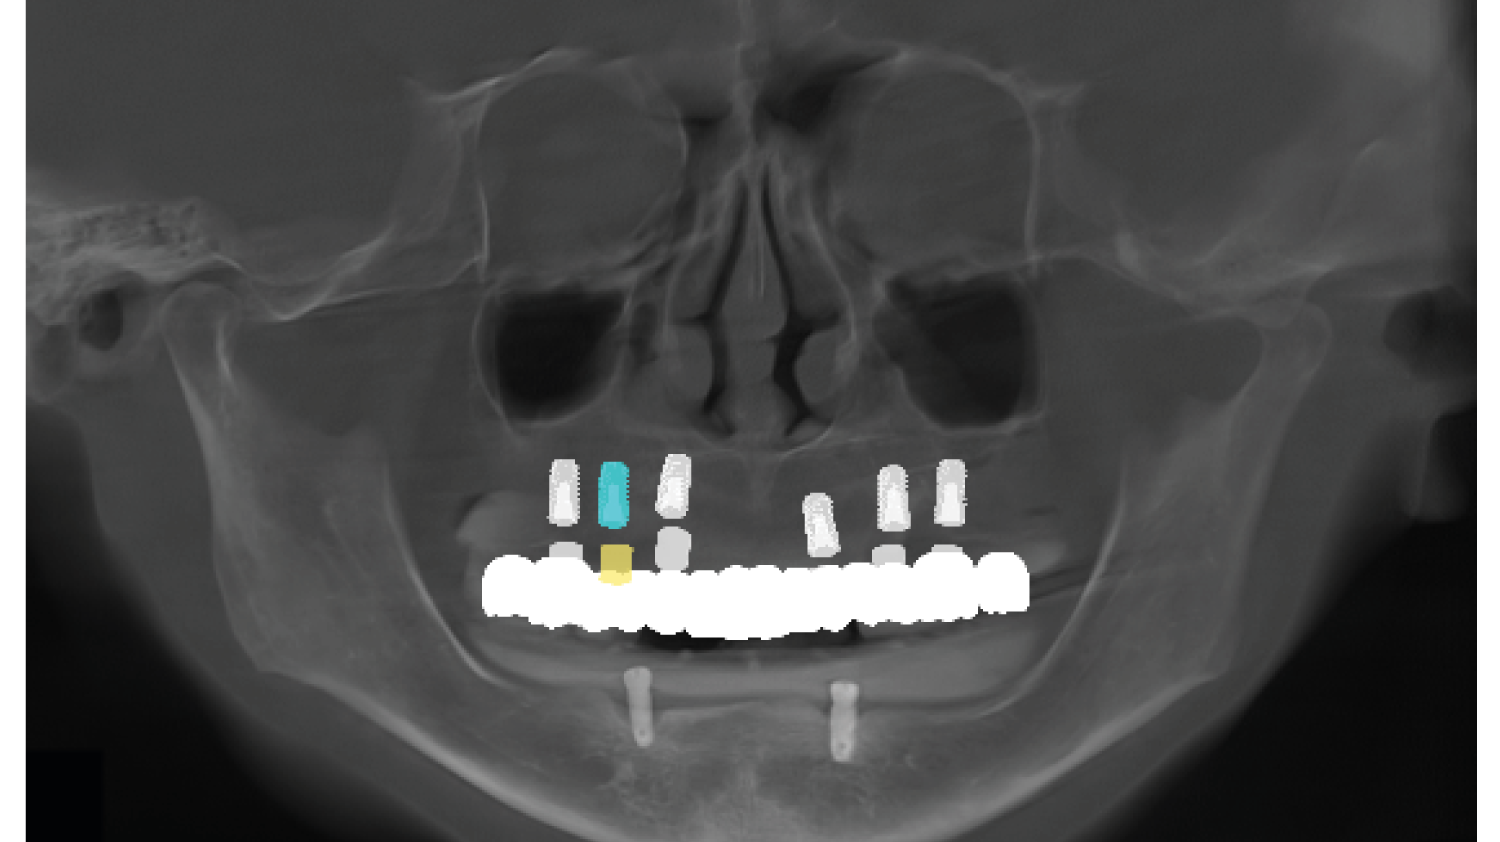

Course Overview

This course presents simplified yet clinically precise workflows for edentulous patients, enhancing both efficiency and patient comfort. Using the JB Tray, participants will learn how to combine custom tray fabrication, final impression, and jaw relation records in a single appointment, supported by digital processing and a live demonstration.

The program also introduces the JB Fork system, which integrates CBCT imaging and anterior reference points to enable one-step surgical stent fabrication without repeated impressions. Through practical demonstrations, attendees will see how this approach streamlines implant surgery while maintaining accuracy. The course concludes with insights into plasma surface treatment in implantology, highlighting its role in advancing clinical outcomes.

• One-Step Surgical Stent Fabrication Using JB Fork and CBCT.

One-Step Surgical Stent Fabrication with JB Fork

• Radiopaque JB Fork and the role of six anterior reference points: Registration with CBCT and integration with facial scanners

• One-step avatar creation without additional clinical procedures

• Surgical stent design and its application in implant surgery

• Live demonstration of JB Fork application in a patient case

Surgical stent design with all guides and implant studio software. (Prof Huh) |

One-Step Surgical Stent Fabrication with JB Fork

• Radiopaque JB Fork and the role of six anterior reference points: Registration with CBCT and integration with facial scanners

• One-step avatar creation without additional clinical procedures

• Surgical stent design and its application in implant surgery

• Live demonstration of JB Fork application in a patient case

Surgical stent design with all guides and implant studio software. (Prof Huh)